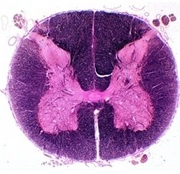

Tracts and Nuclei

Please click one of the following photos to enter the respective section.